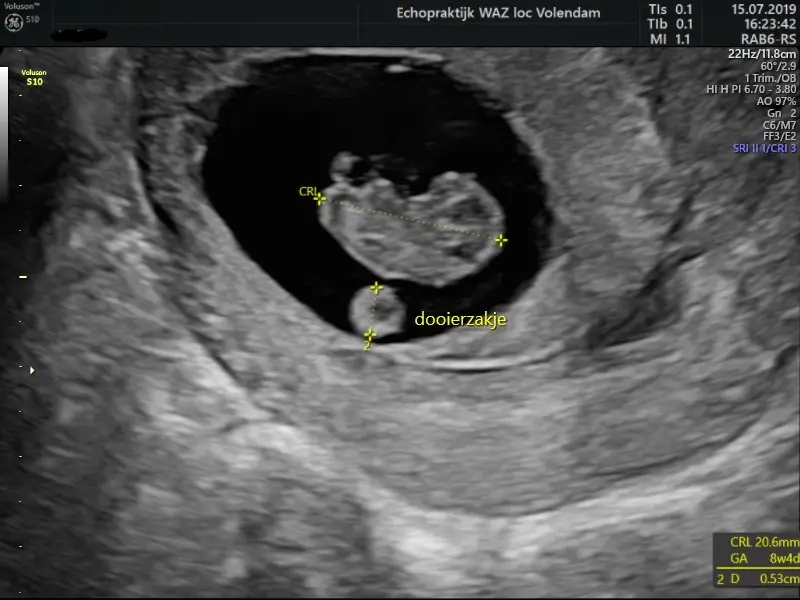

De termijnecho vindt plaats rond de 11 weken. Deze echo heeft als doel je uitgerekende datum vast te stellen (door je kindje op te meten) Baby’s groeien tot 12 weken zwangerschap allemaal in een gelijk tempo. Met 12 weken is de baby helemaal ‘af’ en hoeft hij alleen nog maar te groeien. Een baby wordt gemiddeld genomen geboren tussen 37 en 42 weken, ongeacht je uitgerekende datum. Ook laten we je natuurlijk de hartslag van je kindje horen en zien!

8+ week / 9+ week

8+4wk 21mm